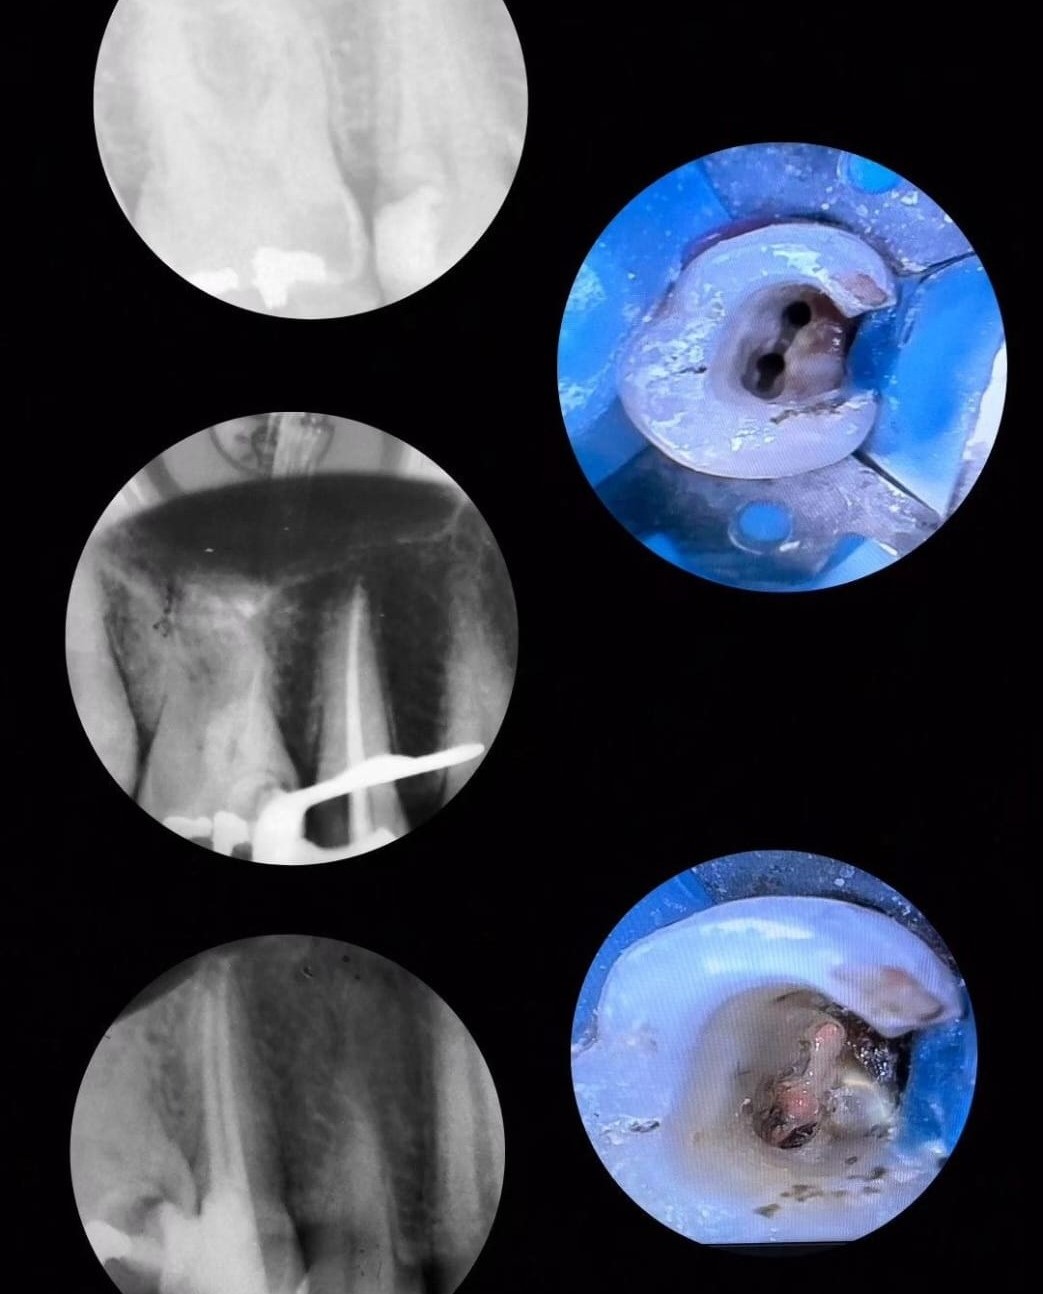

Especialidade principal. Remoção da polpa inflamada para alívio imediato da dor e preservação do dente.